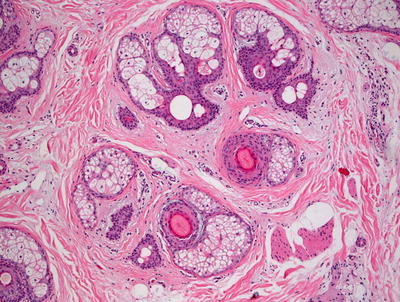

The changes of acne vulgaris include sebaceous hyperplasia and varying degrees of inflammation within and around the pilosebaceous units. Mild cases may demonstrate only a scant lymphohistiocytic infiltrate at the level of the follicular infundibulum with focal follicular spongiosis. More florid cases will show comedones with cystic dilatation of the follicular ostia with keratin plugging (Figs. 10.7 and 10.8). Neutrophilic abscesses can be found within follicular outflow tracts or in the adjacent dermis. Follicular plugging can result in the development of follicular cysts, and in some cases accompanied by marked inflammation. In more extensive cases, there may be disruption of the follicular epithelia, extrusion of keratin into the dermis, and marked inflammation. A granulomatous response with multinucleated giant cells and abundant histiocytes is not unusual in these cases.

Fig. 10.7

Dilated keratin-filled follicles are surrounded by an inflammatory infiltrate in acne vulgaris

Fig. 10.8

Keratin fills a cystically dilated hair follicle in a comedone in acne vulgaris